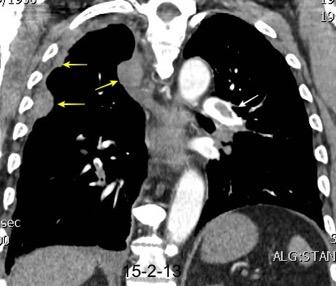

Tromboembolismo pulmonar.

Frecuencia del derrame:

Rx: 32%. TC: 47%

Unilateral. 85%

< 1/3 del hemitórax: 90%

Todos exudados

58% con eritrocitos

21% tabicación lo que causa demora en el diagnóstico

TEP. Empiema pleural. Atelectasia redonda

Porcel JM et al. Analysis of pleural effusions in acute pulmonary embolism: radiological and pleural fluid data from 230 patients. Respirology 2007/ Iguchi T et al. Desquamation of the subpleural lung parenchyma caused by empyema after pulmonary embolism: A case report. Respirol Case Rep. 2022 .